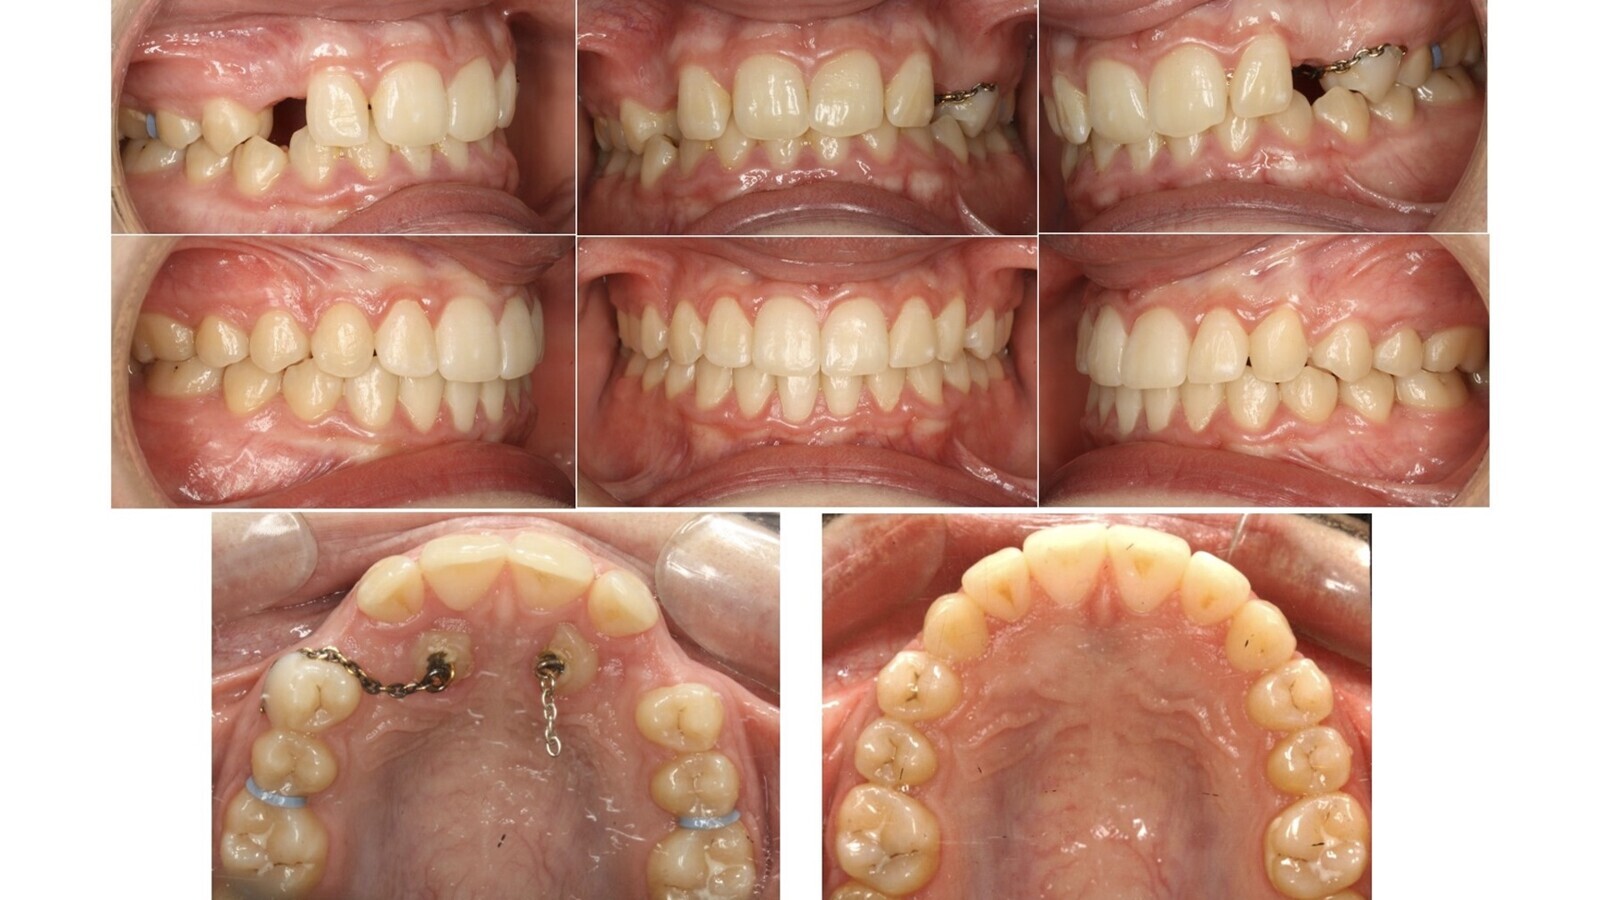

Los cortes transversales de los caninos nos orientan sobre su verdadera inclinación. Los cortes oclusales (figura 9) muestran la relación de vecindad del canino con los incisivos y premolares y si ésta es armoniosa (espacio de seguridad suficiente alrededor de la corona del canino) o presenta signos preocupantes de reabsorción externa de las raíces vecinas.

Figura 9. Los cortes oclusales muestran la relación de vecindad del canino con los incisivos y premolares y si ésta es armoniosa o presenta signos preocupantes de reabsorción externa de las raíces vecinas.

Sobre estos cortes oclusales también establecemos áreas poligonales de mejor (área I) a peor pronóstico (área III), según delimiten las zonas normales de emergencia canina o zonas muy alejadas. La suma de la angulación y la valoración objetiva de cada área ya nos va orientando sobre la mayor o menos dificultad del caso.

Figura 10. Primera valoración espacial tridimensional de los cortes oclusales.